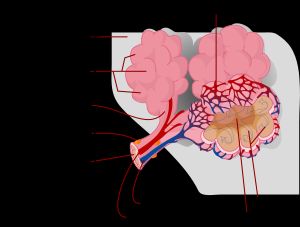

우리의 신체는 폐를 통해 공기 중의 산소를 흡입한다. 코와 입으로 들이마신 산소는 기관지의 가장 끝에 있는 작은 공기주머니인 폐포까지 도달한 후 그 주위에 있는 작은 모세혈관으로 녹아들어 간다. 혈액 속에 녹아들어 간 산소가 심장을 통해 몸의 여러 조직에 공급된다. 반대로 이산화탄소는 모세혈관으로부터 폐포로 나와 다시 호흡을 통해 공기 중으로 배출된다. 간질(間質, interstitium)이란 폐포의 벽에서부터 주위 모세혈관의 벽까지의 공간을 말한다. 산소와 이산화탄소의 교환이 일어나는 벽이라고 할 수 있다. 간질성 폐질환이란 결국 이 공간에 이상이 생기는 것을 말한다.

3. 병태 생리

일반적으로 폐렴(폐포성 폐렴)은 기관지 또는 폐포강 내에서 발생하는 염증을 의미하지만, 간질성 폐렴은 폐포성 폐렴과 달리, 폐포와 모세혈관을 둘러싼 간질이라고 하는 조직에 염증과 섬유화를 일으킨다. 폐포성 폐렴과는 다른 증상과 경과를 보인다.

폐 컴플라이언스의 저하, 즉 "폐가 굳어지는" 상태로, 폐 지지 조직에 염증이 발생하여 비후되면서 폐의 팽창과 수축이 방해받는다. 폐활량이 감소하고, 공기 교환 속도도 느려진다.

간질 조직의 비후로 인해 모세혈관과 폐포가 분리된다. 그 결과, 혈관과 폐포 사이의 가스 교환(확산) 효율이 저하되고, 특히 산소의 확산이 강하게 방해받는다.